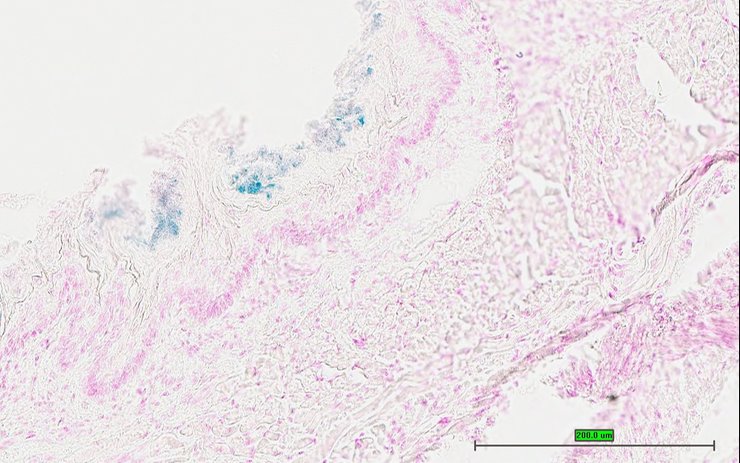

TS28: esophagus Present UC Davis_1880324